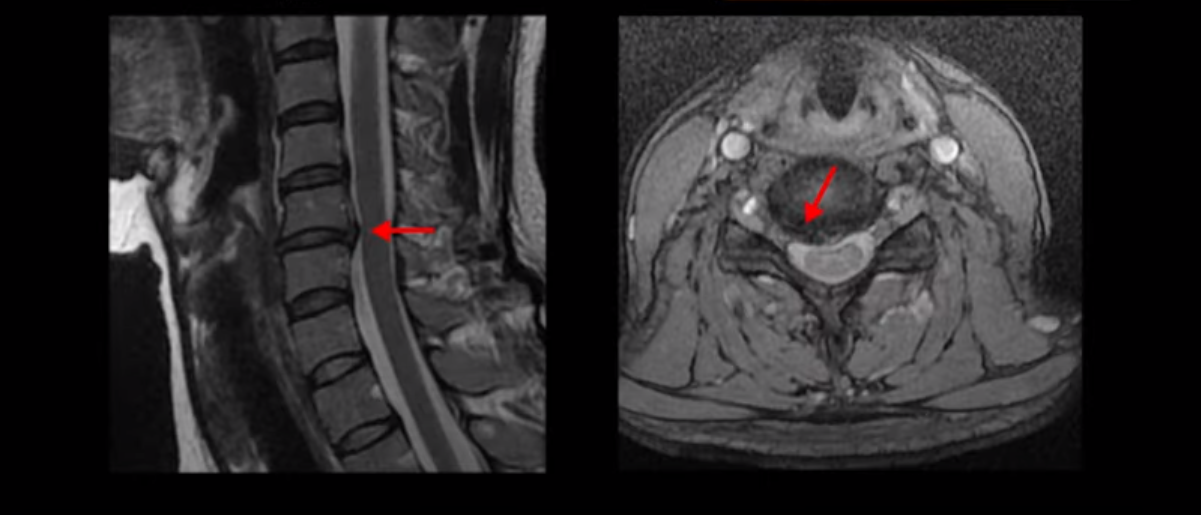

이 환자분 X-ray, MRI 보고 간단히 설명 드린 후 왜 목디스크 치료가 허리디스크에 비해 훨씬 더 쉬운지 자세히 설명 드리겠습니다.

이분 X-ray에서 보시다시피 완전한 일자목과 거북목입니다.

이런 목 형태를 가지면 항상 목이 뻐근하고 담이 걸린 것처럼 아프기 쉽습니다. 그리고 이런 거북목의 형태는 목에 엄청난 부담을 주기 때문에 디스크가 퇴행되면서 언젠가는 찢어지기 쉽습니다. 그래서 결국 5번 6번 목디스크가 찢어지면서 오른쪽으로 밀려나옵니다.

그래서 심한 목통증과 함께 오른쪽 어깨, 오른팔과 손마디가 다 저리고 아픕니다. 아예 목이 안 돌아가고 움직이지 못할 정도로 아파서 빠른 치료를 위해 바로 입원치료를 받으셨는데요. 이분은 목디스크 평균 치료기간인 2주보다 짧은 딱 일주일 입원치료를 받으셨습니다. 어떻게 신경이 눌려 있는 목디스크가 1-2주 만에 좋아질 수 있을까요. 왜 우리는 목디스크가 허리에 비해 훨씬 더 치료가 쉽고 빠르다고 얘기하는 걸까요?

이 환자분도 아까 X-ray에서 보여드렸듯이 아주 심한 일자목, 거북목이 있고 그 결과로 목의 거의 모든 마디가 다 퇴행이 진행되어 있죠. 즉 거북목은 모든 목질환, 특히 목디스크, 목협착증의 어머니 질환이며 그래서 목디스크를 치료하기 위해서는 반드시 거북목 때문에 짧아지고 뭉치고 굳고 뒤틀린 목 주변 근육들을 잘 치료해줘야 합니다.